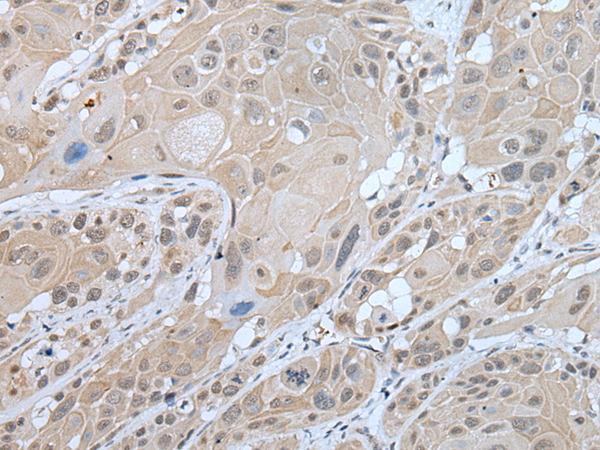

分类: 科研抗体货号: P02361别名: RNTRE; TRE2NL; USP6NL-IT1应用: WB,IHC反应种属: Human